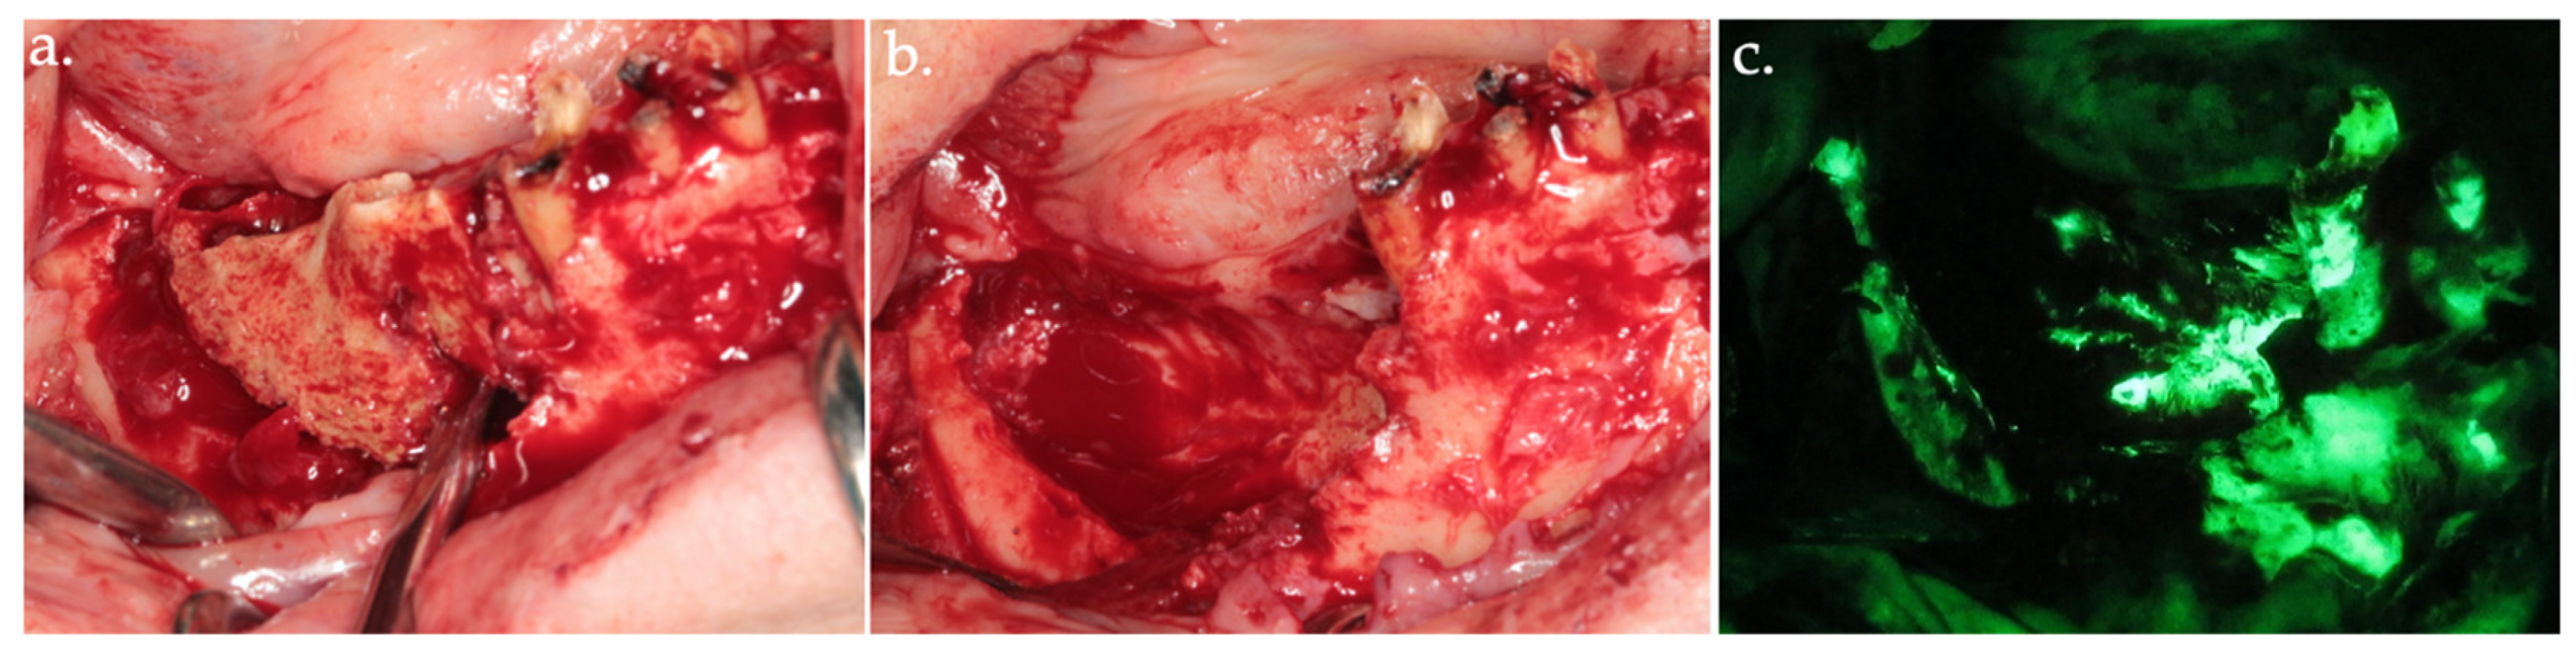

2.2. Autofluorescence-Guided Surgery